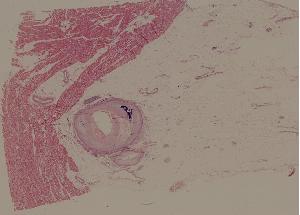

46. Coronary atherosclerosis